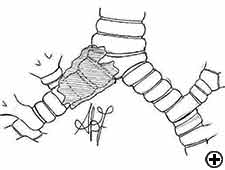

Carinal resection is a complex and aggressive procedure for the treatment of bronchial tumors involving the carina, the tracheo-bronchial angle or the distal portion of the trachea (Figure 1). The airway is reconstructed by anastomosis of the opposite main bronchus (tracheal sleeve pneumonectomy) or both bronchi (isolated carinal resection) to the lower trachea (Figure 2). The most common indication for a sleeve pneumonectomy is a tumor involving the origin of right main bronchus or extending into the lower trachea. Left sleeve pneumonectomy is rarely indicated since the left main bronchus is considerably longer than the right one and, in the case of carinal infiltration, tumor usually invades the structures in the subaortic space as well, which frequently implies inoperability. An isolated carinal resection and reconstruction may be applicable for centrally located, low grade and small tumors of the carina not extending so far to the main bronchi. Carinal resection represents a challenge for thoracic surgeons and anesthesiologists related to demanding intraoperative airway management, the technique of anatomic reconstruction and the risk of significant postoperative morbidity, mortality and poor long-term outcome [11].

In isolated carinal resection and reconstruction, applicable for centrally located, low grade and small tumors (Video 8), the right and left main bronchi can be medially sutured to create a new carina, that is subsequently anastomosed to the distal trachea (Figure 2C and Video 9). A less common technique provides the resection of the carina followed by an end-to-end anastomosis between the left main bronchus and the trachea, followed by anastomosis of the right main bronchus to the lateral, cartilaginous wall of the trachea, paying attention to stay at least 2 cm above the first anastomosis (Figure 6). When more advanced tracheal involvement is present, two alternative techniques may be used to avoid excessive tension: an end-to-end anastomosis between the right main bronchus and the trachea, followed by anastomosis of the left main bronchus to the lateral, cartilaginous wall of the bronchus intermedius or an end-to-end anastomosis between the left main bronchus and the trachea, followed by anastomosis of the right main bronchus to the lateral, cartilaginous wall of the left main bronchus (Figure 7). In all of cases a wide hilar release is mandatory to reduce tension on the anastomoses.